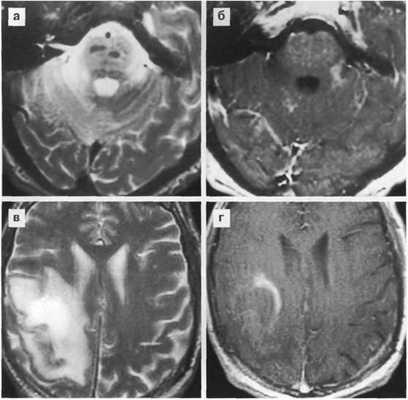

МРТ без и с контрастным усилением

- Более чувствительная как к новым, так и к хроническим проявлениям токсоплазмозного энцефалита и выявляет большее количество образований, чем КТ.

- На МРТ в режиме Т2 активные очаги имеют вариабельный МР сигнал:

- — гиперинтенсивнее вещества мозга и не отличаться от зоны отека.

- — изо- или гипоинтенсивный в центре очаг поражения, окруженный зоной отека, получивший название «мишени».

Токсоплазмоз у ВИЧ-инфицированного больного

МРТ в режиме Т2 (а,б) и Т1 с контрастированием (в-е) выявляет множественные очаговые изменения с накоплением контраста - симптом «мишени». В правом полушарии мозжечка образование по характеристиками похожее на абсцесс.